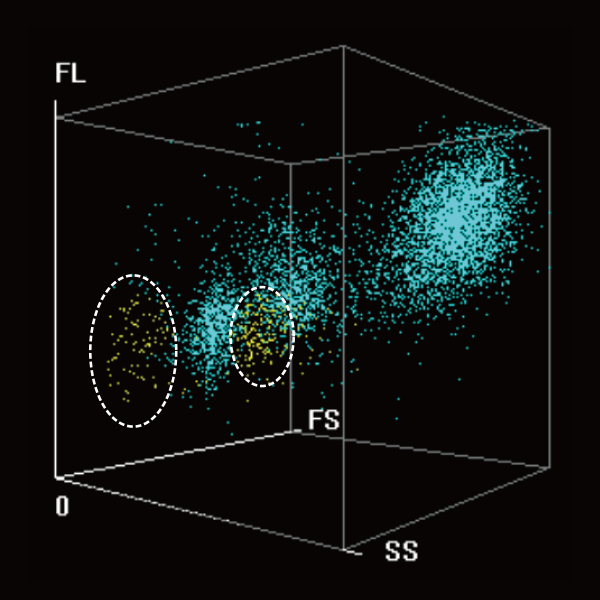

The coordinated analysis technology of WNB and DIFF scattergarms give sensitive alerts for РђюBlasts" with high specificity to reduce unnecessary labor-intensive manual microscopy.

DIFF 3D scattergram

Coordinated analysis

WNB 3D scattergram

Abn. Lymph/blast?

Abn. Promyelocyte/blast?

The detection concentration is as low as 0.03├Ќ10?/L